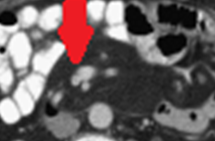

CT κοιλίας. Κόκκινο βέλος — Τυφλίτιδα. Σημαντική πάχυνση τοιχώματος τυφλού (Ευγενική παραχώρηση Dr. V. Penopoulos)